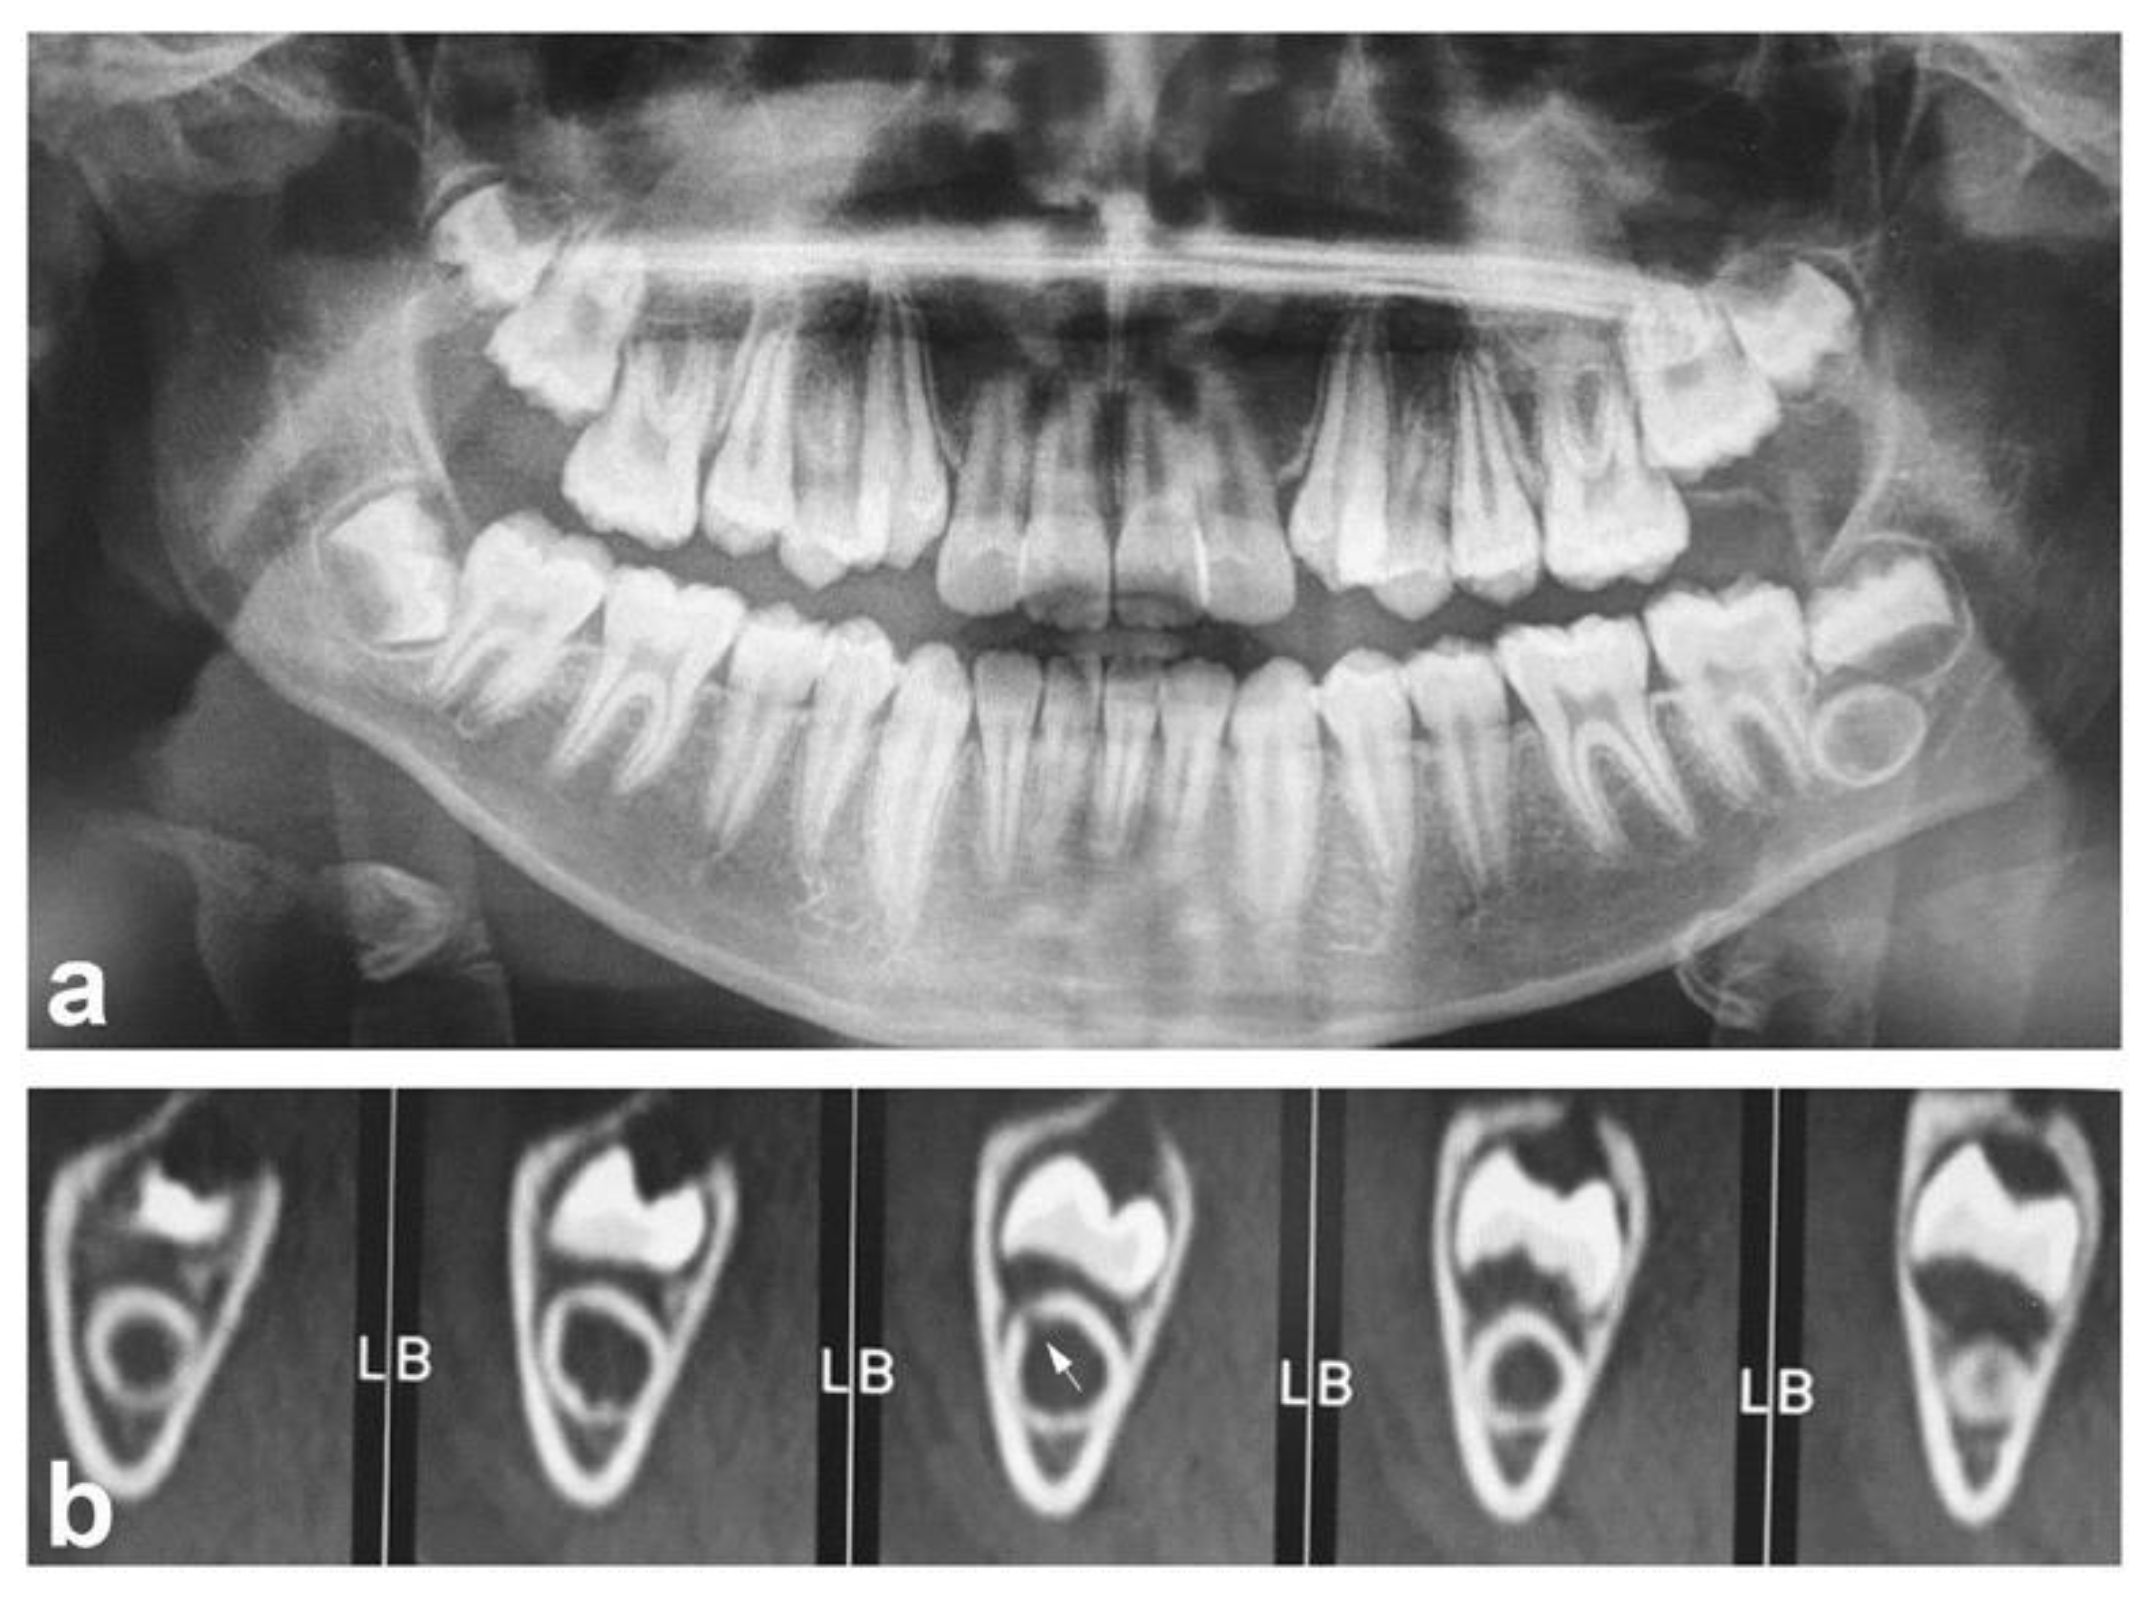

Dilated Odontoma Arising in the Mandibular Third Molar Germ: Report of a Case of an Unusual Lesion in an Uncommon Site

2. Case Report

- Cuković-Bagić, I.; Macan, D.; Dumancić, J.; Manojlović, S.; Hat, J. Dilated odontome in the mandibular third molar region. Oral Surg. Oral Med. Oral Pathol. Oral Pathol. Endod. 2010, 109, 109–113. [Google Scholar] [CrossRef] [PubMed][Green Version]

| 11 years/Male | Asymptomatic | 3.8 (germ tooth) | Present case |